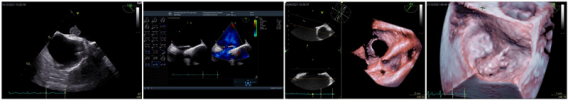

经食管超声心动图(TEE)是近年发展起来的心血管超声新技术,是将超声探头置入食管内,从心脏后方近距离观察心脏的解剖结构与功能,与经胸超声相比,可以提供更高品质的图像和更多有价值的临床信息。此技术已经广泛应用于临床,是心血管疾病重要诊查手段之一。该技术的主要适应症包括:

我科在西南地区率先开展TEE检查,迄今已经完成TEE检诊数量超过数万例,积累了丰富的临床经验。